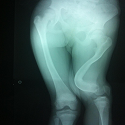

Association très rare: fracture de la diaphyse fémorale associée à une fracture de Hoffa homolatérale

Issam Elouakili, Younes Ouchrif

PAMJ. 2014; 19: 223. Published 29 October 2014